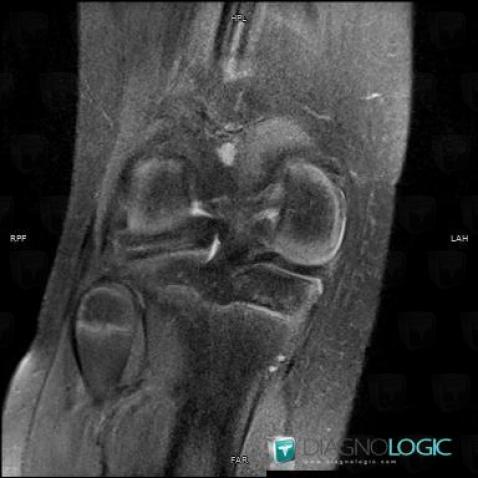

Discoid meniscus , Meniscus, MRI

Here is the specific information in the key image above:

- Diagnosis Discoid meniscus , Location(s) Meniscus, with gamuts Meniscal injury